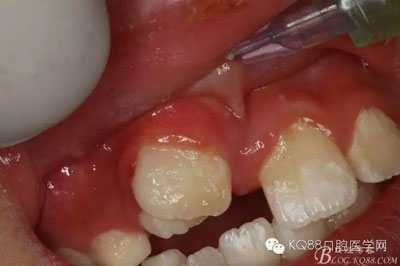

圖1.術(shù)前的患者口內(nèi)照片:11與12完全唇腭向重疊,11與21之間有3mm間隙

圖4.局部粘膜先涂表麻膏